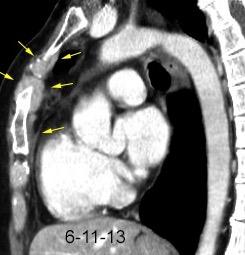

102. HEMATOMA MEDIASTÍNICO.

Hematoma retroesternal y pericárdico en cirugía de válvula mitral. Migración de suturas